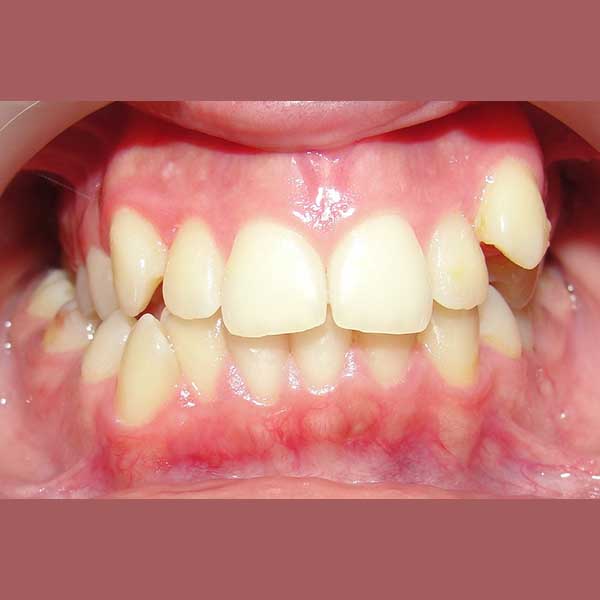

BEFORE

راجعتني هذه الشابة وهي تعاني من ازدحام شديد في أسنانها، كان أبرز مظاهره بزوغ أحد أنيابها بشكل مرتفع وبعيد جداً عن مكانه الطبيعي في القوس السني. كان طلبها واضحاً: الحصول على ابتسامة مرتبة ولكن مع تجنب قلع أي أسنان.